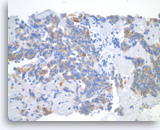

Plasma cell neoplasm,

Pancreas FNA, Cell Block.

Single tumor cells show eccentric nuclei and occasional binucleation. Flow cytometry demonstrate CD38 positive B-cells without surface immunoglobulin expression. The cytomorphologic features along with flow cytometry results are consistent with plasma cell neoplasm. CD138 immunostain can be performed on the cell block section to support the diagnosis if needed.

40X

Plasma cell neoplasm,

Pancreas FNA, Cell Block.

Single tumor cells show eccentric nuclei and occasional binucleation. Flow cytometry demonstrate CD38 positive B-cells without surface immunoglobulin expression. The cytomorphologic features along with flow cytometry results are consistent with plasma cell neoplasm. CD138 immunostain can be performed on the cell block section to support the diagnosis if needed.

40X